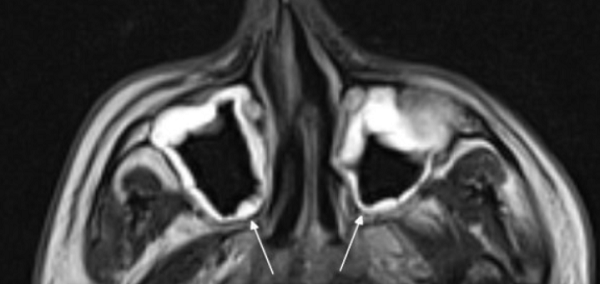

На снимке концентрическая воспалительная гипертрофия (указана стрелками) слизистой оболочки гайморовых пазух

Компьютерную томографию применяют для изучения строения костной ткани и выявления патологической жидкости в синусах носа. Исследование пазух на магнитном аппарате дает информацию о состоянии слизистых оболочек, отражает наличие новообразований. Отталкиваясь от того, что показывает МРТ пазух носа, врач может составить для пациента прогноз и назначить лечение. Процедура безопасна и высокоинформативна.